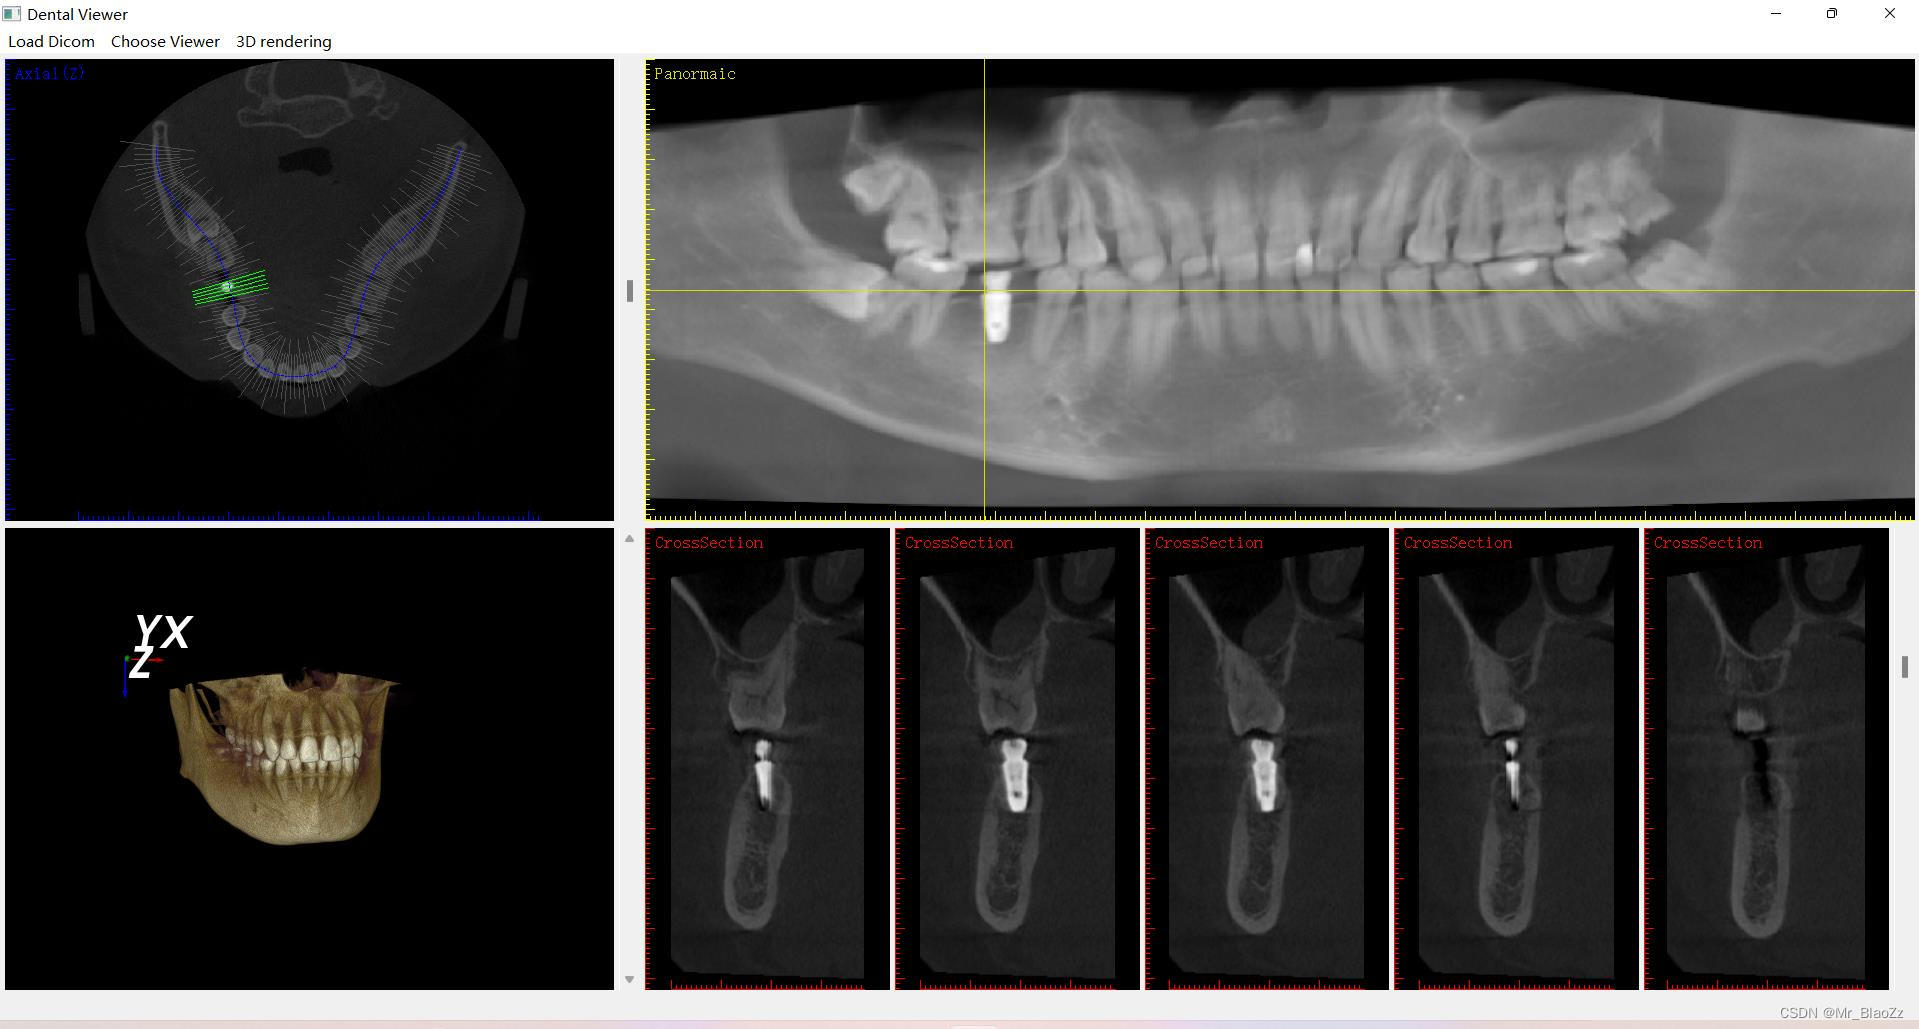

这次仿照一个软件的布局,实现了这款软件的大部分功能,功能大致差不多,主要使得整个界面布局以及内容更加完善,主要包含三个界面:三维视图、全景视图、种植视图。同时,也稍微了解下vtk库,实现了三维重建,基本了解了vtk的坐标系原理、坐标值、vtk空间中的各种绘制等等,但这些代码还没有完全整理出来。测试了三维模型的实时更新占用内存较多。后续会逐渐向vtk三维空间和界面交互方面完善。

ps:对于之前有些人一直问关于这个界面的部分,其实把CT数据当成一个长方体,用三把刀从上下、前后、左右三个方向去切这个长方体,然后三个面交于长方体内一点,就可以很好理解MPR图像了。另外,这里所有一个界面内所有视图都是联动的!由于本人未还未毕业暂不公布源码,有兴趣的可以评论交流就行。

仿造软件布局实现大部分功能,包括三维、全景和种植视图。初步掌握vtk库进行三维重建,理解坐标系原理。注意到三维模型实时更新内存消耗大,计划改进交互与界面。CT数据解释MPR图像原理,所有视图联动,未公开源码,欢迎交流。

仿造软件布局实现大部分功能,包括三维、全景和种植视图。初步掌握vtk库进行三维重建,理解坐标系原理。注意到三维模型实时更新内存消耗大,计划改进交互与界面。CT数据解释MPR图像原理,所有视图联动,未公开源码,欢迎交流。